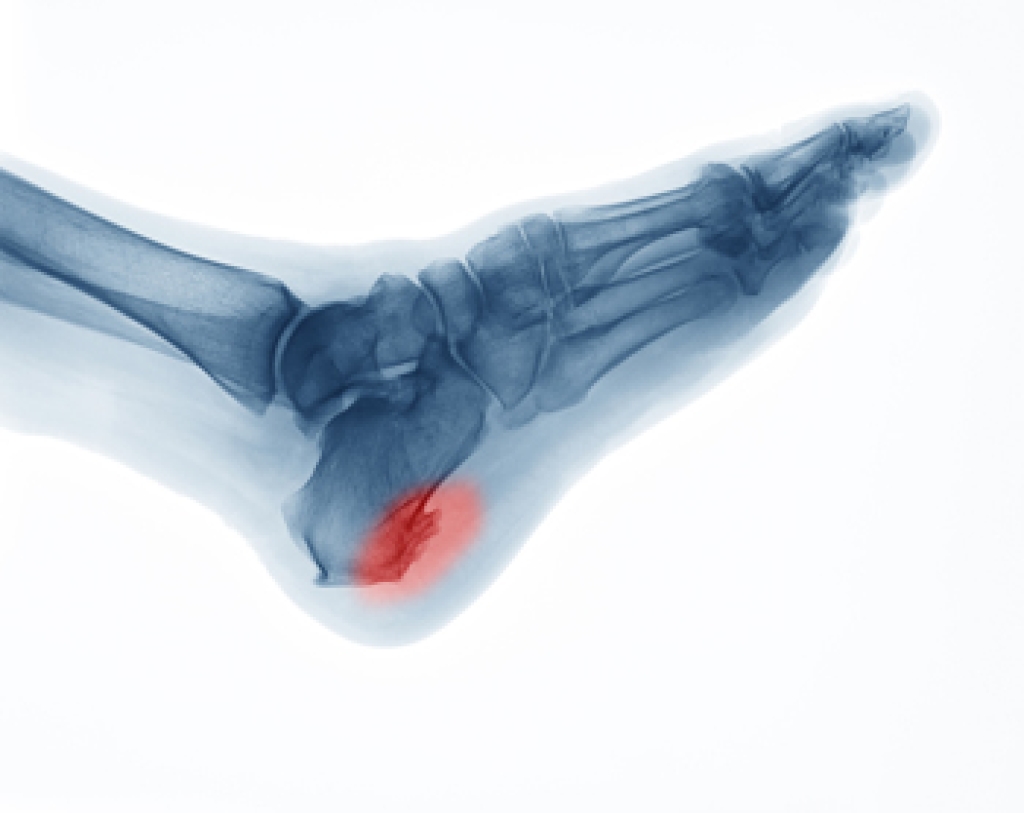

What Is a Heel Spur?

A heel spur is a growth of bone that forms from extra calcium deposits on the foot and that stretch from the heel bone to the foot arch. It is one of the most common causes of heel pain. Heel spurs are a quarter of an inch in length or smaller, though they may become larger in some cases. They cannot be seen from outside of the body but can become quite painful, especially when jumping, running, or walking. There may be swelling of the heel and ankle with heel spurs. Some of the primary causes of heel spurs are ill fitting or non-supportive footwear, wearing high heels, bruising under the heel bone, poor posture or other physical structural issues (such as flat feet or high arches), or being overweight or obese. Other possible causes are having a pre-existing medical condition, like diabetes or arthritis, over-training, repetitive hard impact or pressure on the heel, and aging with calcium leaving the bones and settling into the bloodstream and attaching to the surface of bones. Women are more prone to developing heel spurs than men because their hips are naturally wider in comparison to their knees which causes additional pressure to be placed on the heel with movement. Routine foot care and exercises to reduce ligament stress and relieve bone tension will help invigorate heel tissues, but sometimes surgery will be required to remove a heel spur. If you have a heel spur and it is causing pain and interfering with your functioning, consult with a podiatrist who can recommend the best course of treatment.

Heel spurs can be incredibly painful and sometimes may make you unable to participate in physical activities. To get medical care for your heel spurs, contact one of our podiatrists from Pennsylvania Foot & Ankle. Our doctors will do everything possible to treat your condition.

Heels Spurs

Heel spurs are formed by calcium deposits on the back of the foot where the heel is. This can also be caused by small fragments of bone breaking off one section of the foot, attaching onto the back of the foot. Heel spurs can also be bone growth on the back of the foot and may grow in the direction of the arch of the foot.

Older individuals usually suffer from heel spurs and pain sometimes intensifies with age. One of the main condition's spurs are related to is plantar fasciitis.

Pain

The pain associated with spurs is often because of weight placed on the feet. When someone is walking, their entire weight is concentrated on the feet. Bone spurs then have the tendency to affect other bones and tissues around the foot. As the pain continues, the feet will become tender and sensitive over time.

Treatments

There are many ways to treat heel spurs. If one is suffering from heel spurs in conjunction with pain, there are several methods for healing. Medication, surgery, and herbal care are some options.